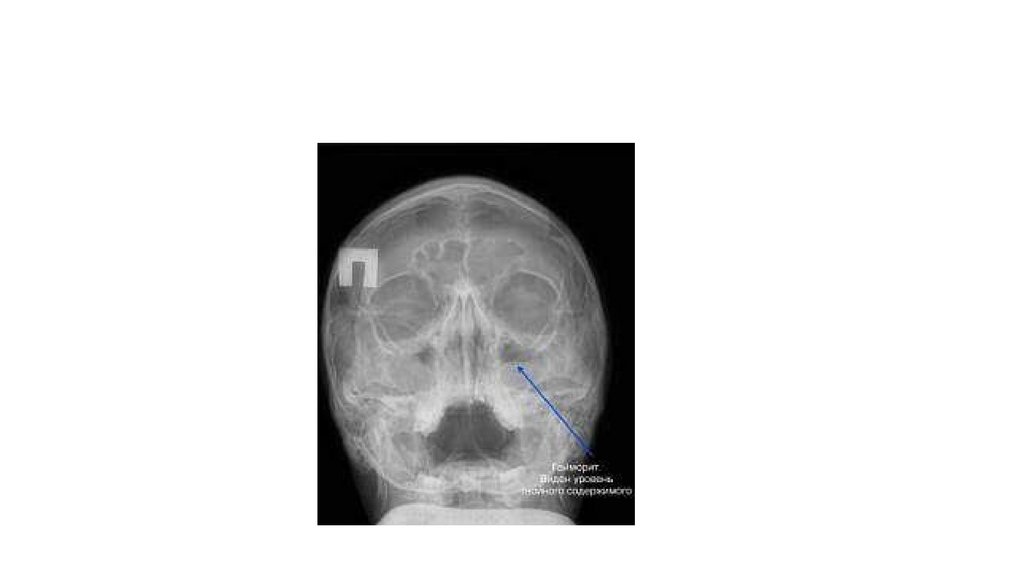

Какие процедуры/методы осмотра(обследования) изображены на фото?